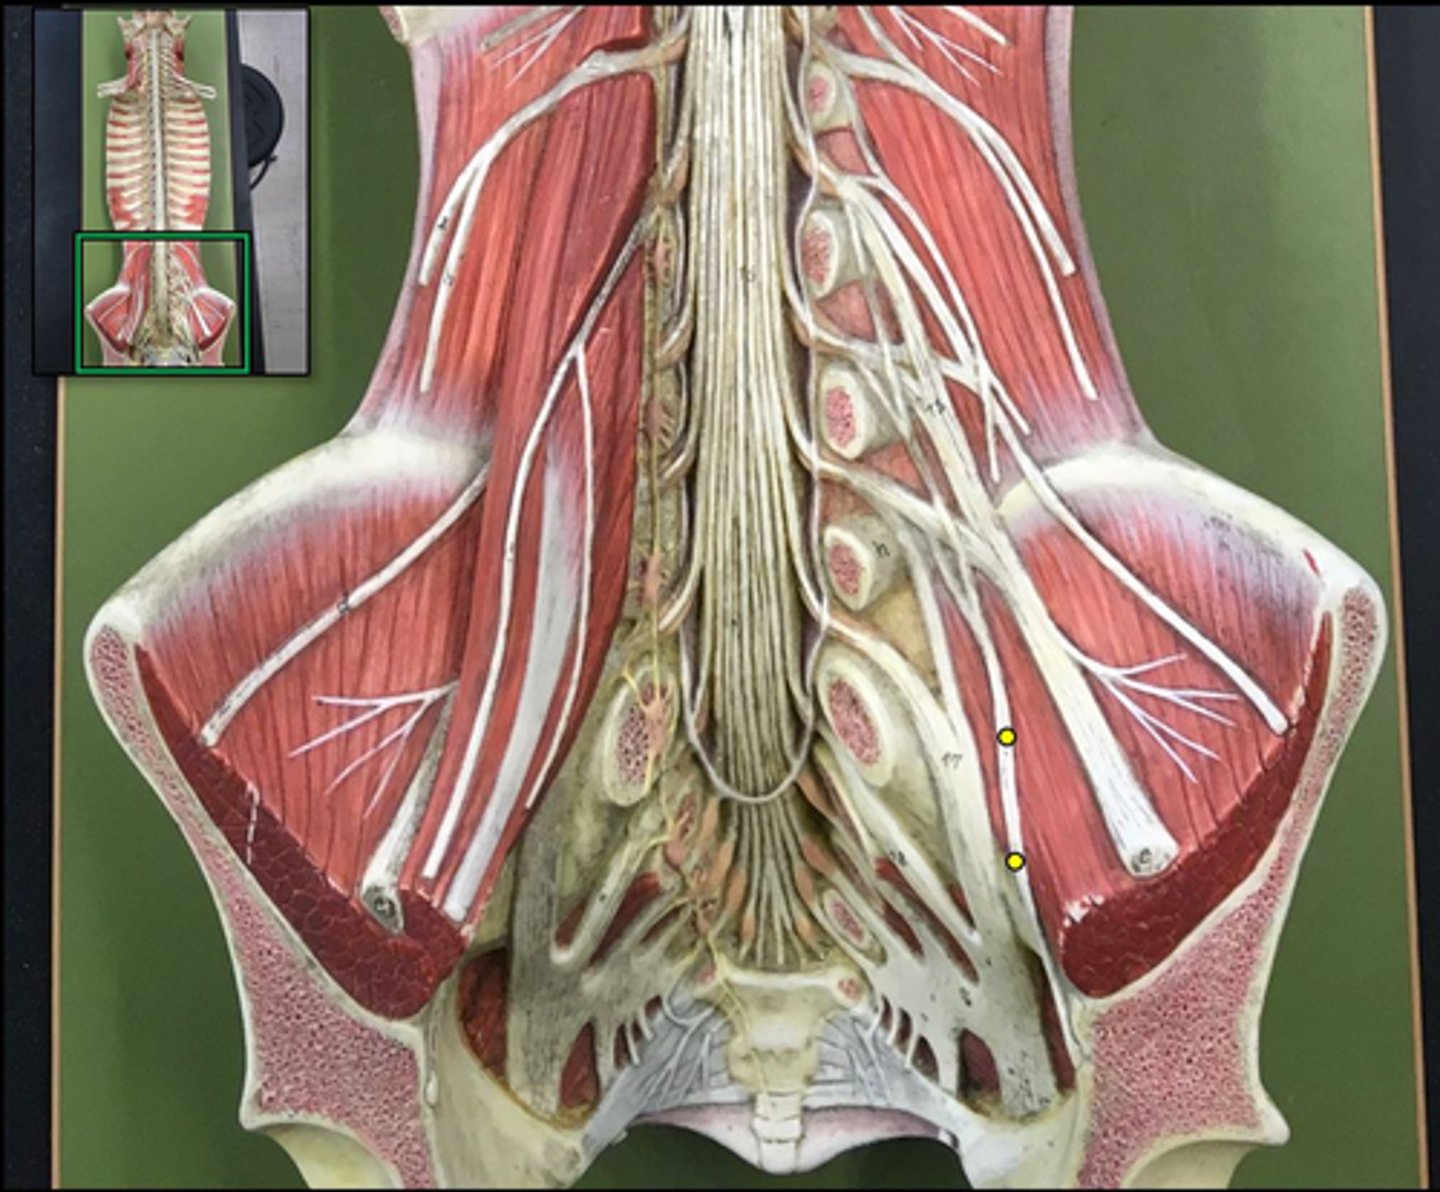

cauda equina

bundle

lumbar plexus

T12- L4

sacral plexus

L4- S4

genitofemoral nerve

Wishbone of the leg

lateral femoral cutaneous nerve

femoral nerve

saphenous nerve

posterior femoral cutaneous nerve

sciatic nerve

obturator nerve